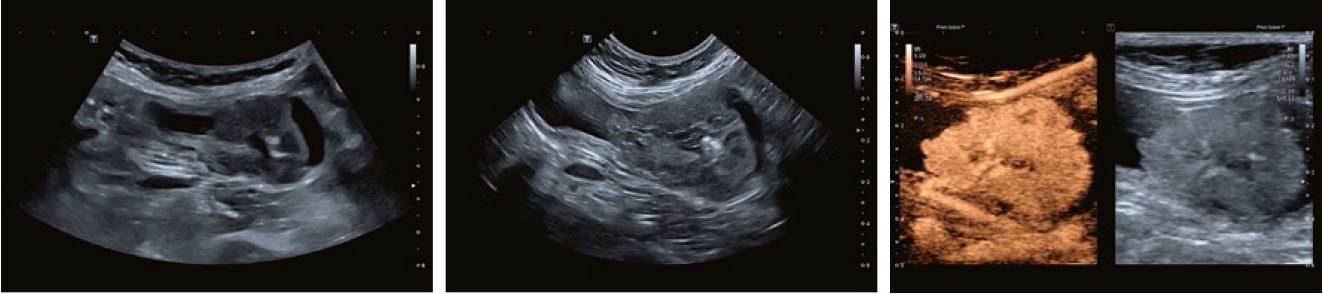

Огляд черевної порожнини собаки в 2D-режимі з

візуалізацією надниркових залоз.

Випадок 1

Французький бульдог, десятирічний; поступив з хронічною блювотою і втратою ваги; біохімія крові в нормі, лейкоцити низькі (2400); УЗД з різко гіпоехогенними, неправильної форми ураженнями в печінці і головці підшлункової залози, круглим вогнищем в області правого наднирника; CEUS 2,5 мл Sonoview, датчик 11L3 вимивання уражень печінки через 3,45 хв, на жаль, підсилення надто високе, але все ще діагностоване; евтаназія через два місяці